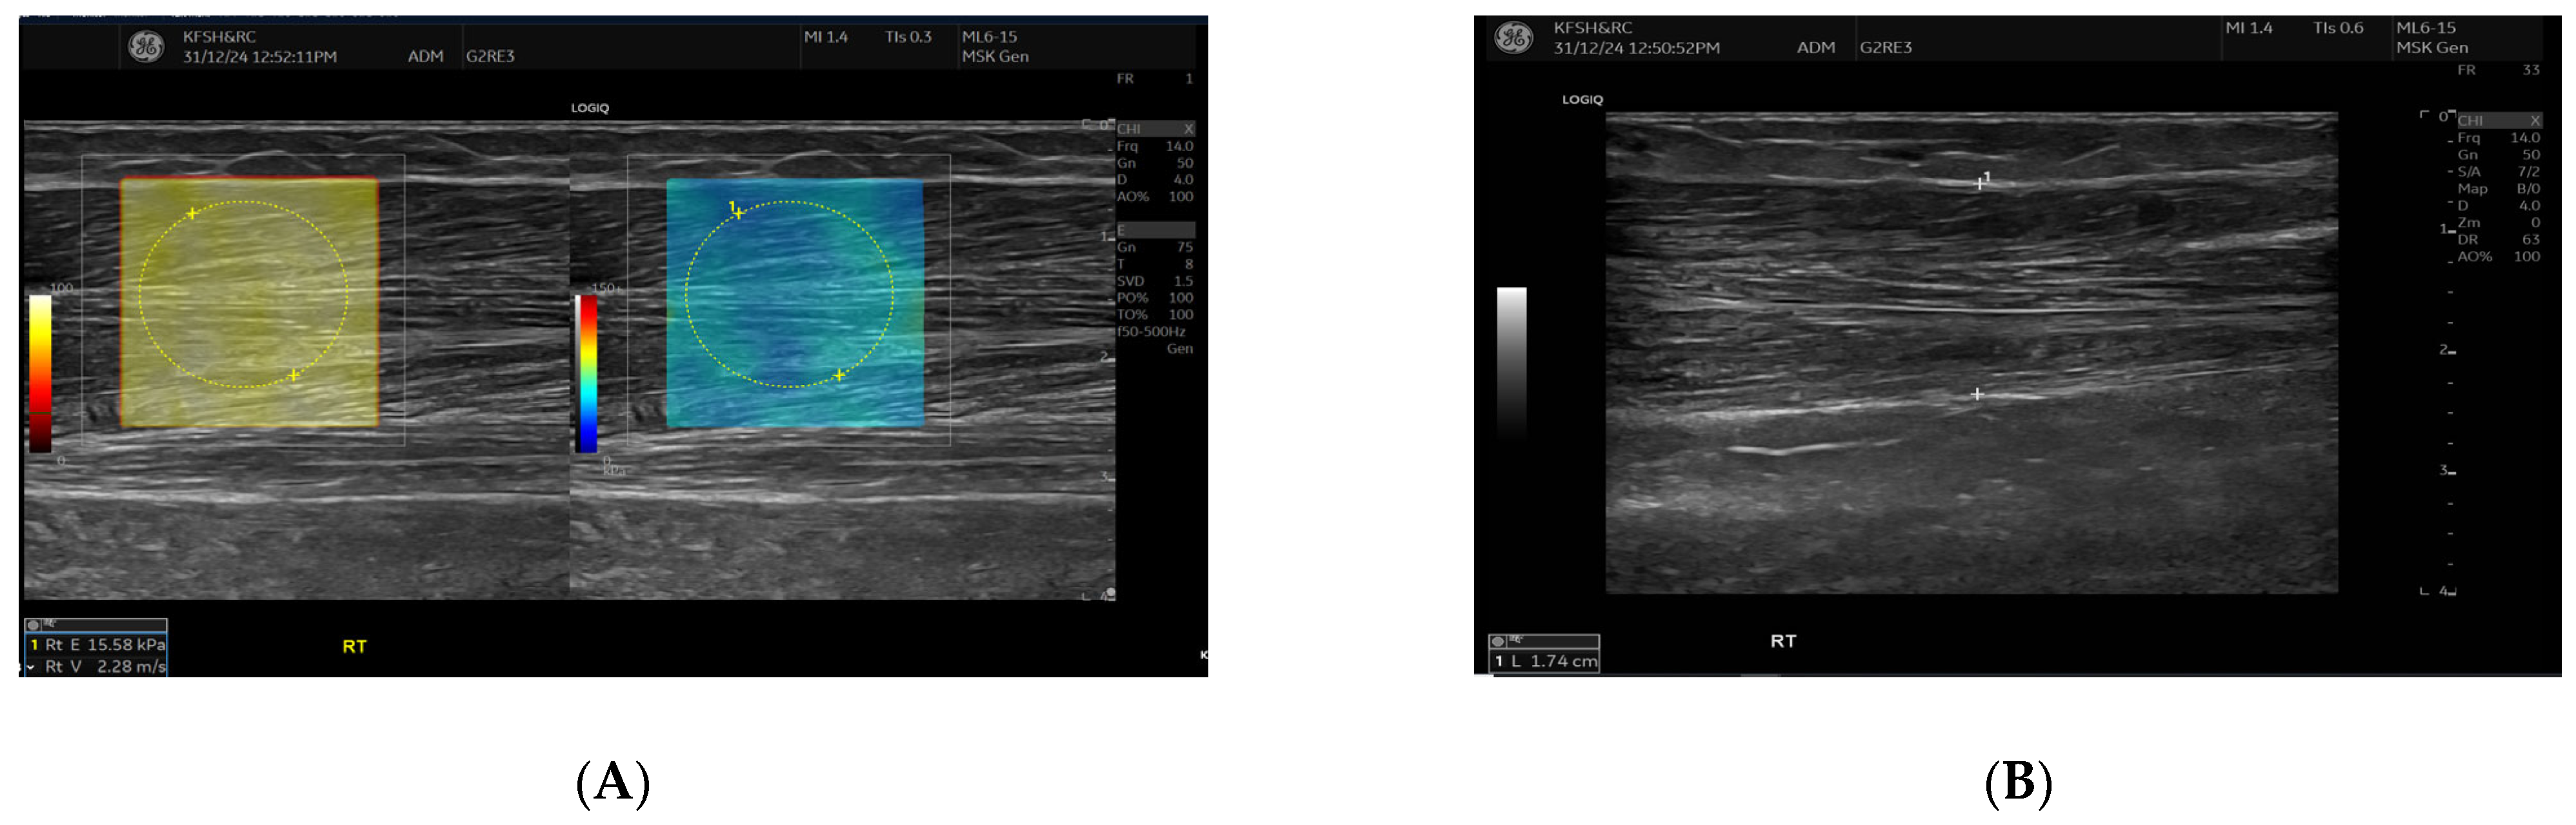

SWE measurements were acquired using a GE LOGIQ E10 (GE HealthCare, Chicago, IL, USA) system equipped with an ML 6-15 D linear transducer (frequency 6–15 MHz). Depth settings were standardized at 2.5–3.5 cm depending on muscle thickness. Each ROI was circular with a 5–7 mm diameter, placed centrally within the elastograms, avoiding fascia, vascular structures, and visible artefacts. Stiffness values were recorded in both kilopascals and metres/second, although statistical analyses were conducted using shear-wave velocity (m/s) for consistency. Frames with motion or colour dropout were discarded and reacquired. Muscle stiffness and thickness were evaluated in the biceps brachii and brachioradialis muscles, located proximal to the AVF site, Figure 1 and Figure 2. SWE imaging provided both Colour-coded elastograms and quantitative stiffness measurements (m/s; Figure 3). Participants were examined supine, with the shoulder in neutral rotation, the elbow extended to approximately 10–20°, and the forearm supinated. This minimized passive tension, which can influence shear-wave velocity. The transducer was positioned perpendicular to the muscle fibres, capturing measurements from the proximal, middle, and distal regions for comprehensive analysis. Measurements were taken before the haemodialysis to avoid intravascular volume shifts, with each parameter recorded three times and averaged for precision. Scans were performed by an experienced sonographer and verified by a radiologist, minimizing bias. A preliminary review of some patient records was conducted to refine data collection tools before the main data collection.

Figure 2.

This figure demonstrates the comparison of brachioradialis muscle thickness between the fistula (A) and the contralateral arm (B). B-mode ultrasound images showing brachioradialis muscle thickness measurements. The left panel (A) (fistula side) demonstrates reduced muscle thickness (1.14 cm) compared with the contralateral arm (right panel (B), 1.74 cm). Measurements were obtained in the mid-muscle belly using a linear high-frequency transducer.